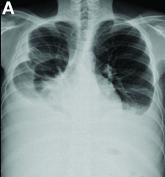

OpinionWhat is your diagnosis? - January 2019Author:Ching-Pin Lin, MDPublish date: January 1, 2019Clinical Challenges - January 2019Read More